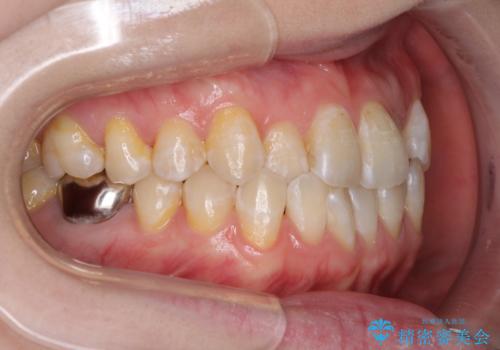

前歯のデコボコを治したい インビザラインによる矯正治療

- 前歯のデコボコを治したいとのことで来院された患者様です。

上下顎ともに歯列全体の後方移動とIPR(歯と歯の間を削る)によってデコボコが解消するように設計し、インビザラインにより治療を行うこととしました。

1日22時間の装着時間をほとんど達成することができず、治療には当初予定の2倍以上の期間を要することとなりました。